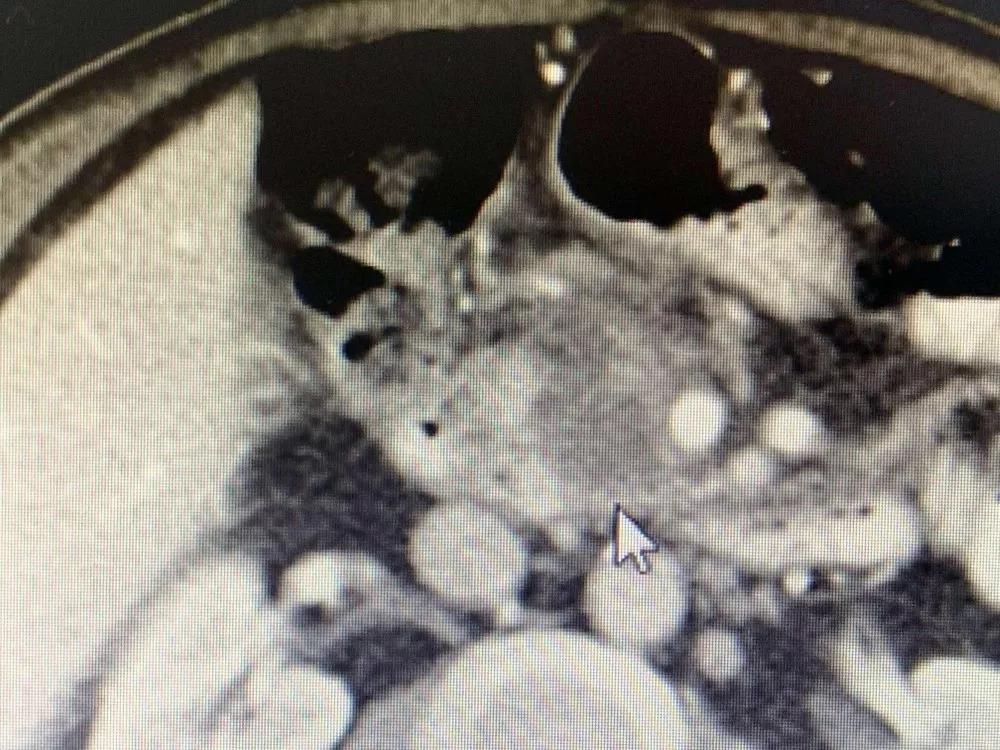

今天早上九点十五分,天气晴朗,牛立志博士和李红梅医生前脚后脚的踏入了602病房,走进去时候,一头橘红色卷发的梭盘坐在在床上,和身旁的家人有说有笑,看见牛博士和李医生到来,梭深感高兴。李医生说道:“74岁的尼泊尔ranten先生,胰腺癌纳米刀消融手术后一周,复查CT肿瘤完全坏死,肿瘤标志物CA199从术前的78降至正常。”

手术后

牛立志博士查阅梭的检查报告点了点头,翻阅梭的影像及化验情况不错,轻轻的拍着梭的肩膀耳旁说道“梭,告诉你一个好消息,你明天可以出院了。”梭激动的握住牛博士的手,把牛博士的手放在他的额头上,嘴里念叨着。正当牛博士表示疑惑看着他家属时,家属笑着解释道:“这是尼泊尔的一种礼节,是为了表示感谢牛博士。在来复大肿瘤医院之前,我们也曾咨询了印度等国家医生,他们都表示没有办法,来中国我们也是半信半疑,毕竟这么多医生都不肯接,没想到梭在进行纳米刀手术后,恢复那么快,症状也得到改善了,太感谢牛博士给予了我们一家生的希望。”